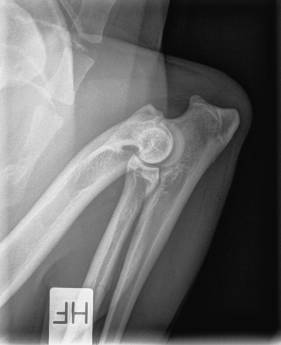

AD Højre 0

AD Venstre 0

AD: 0/0